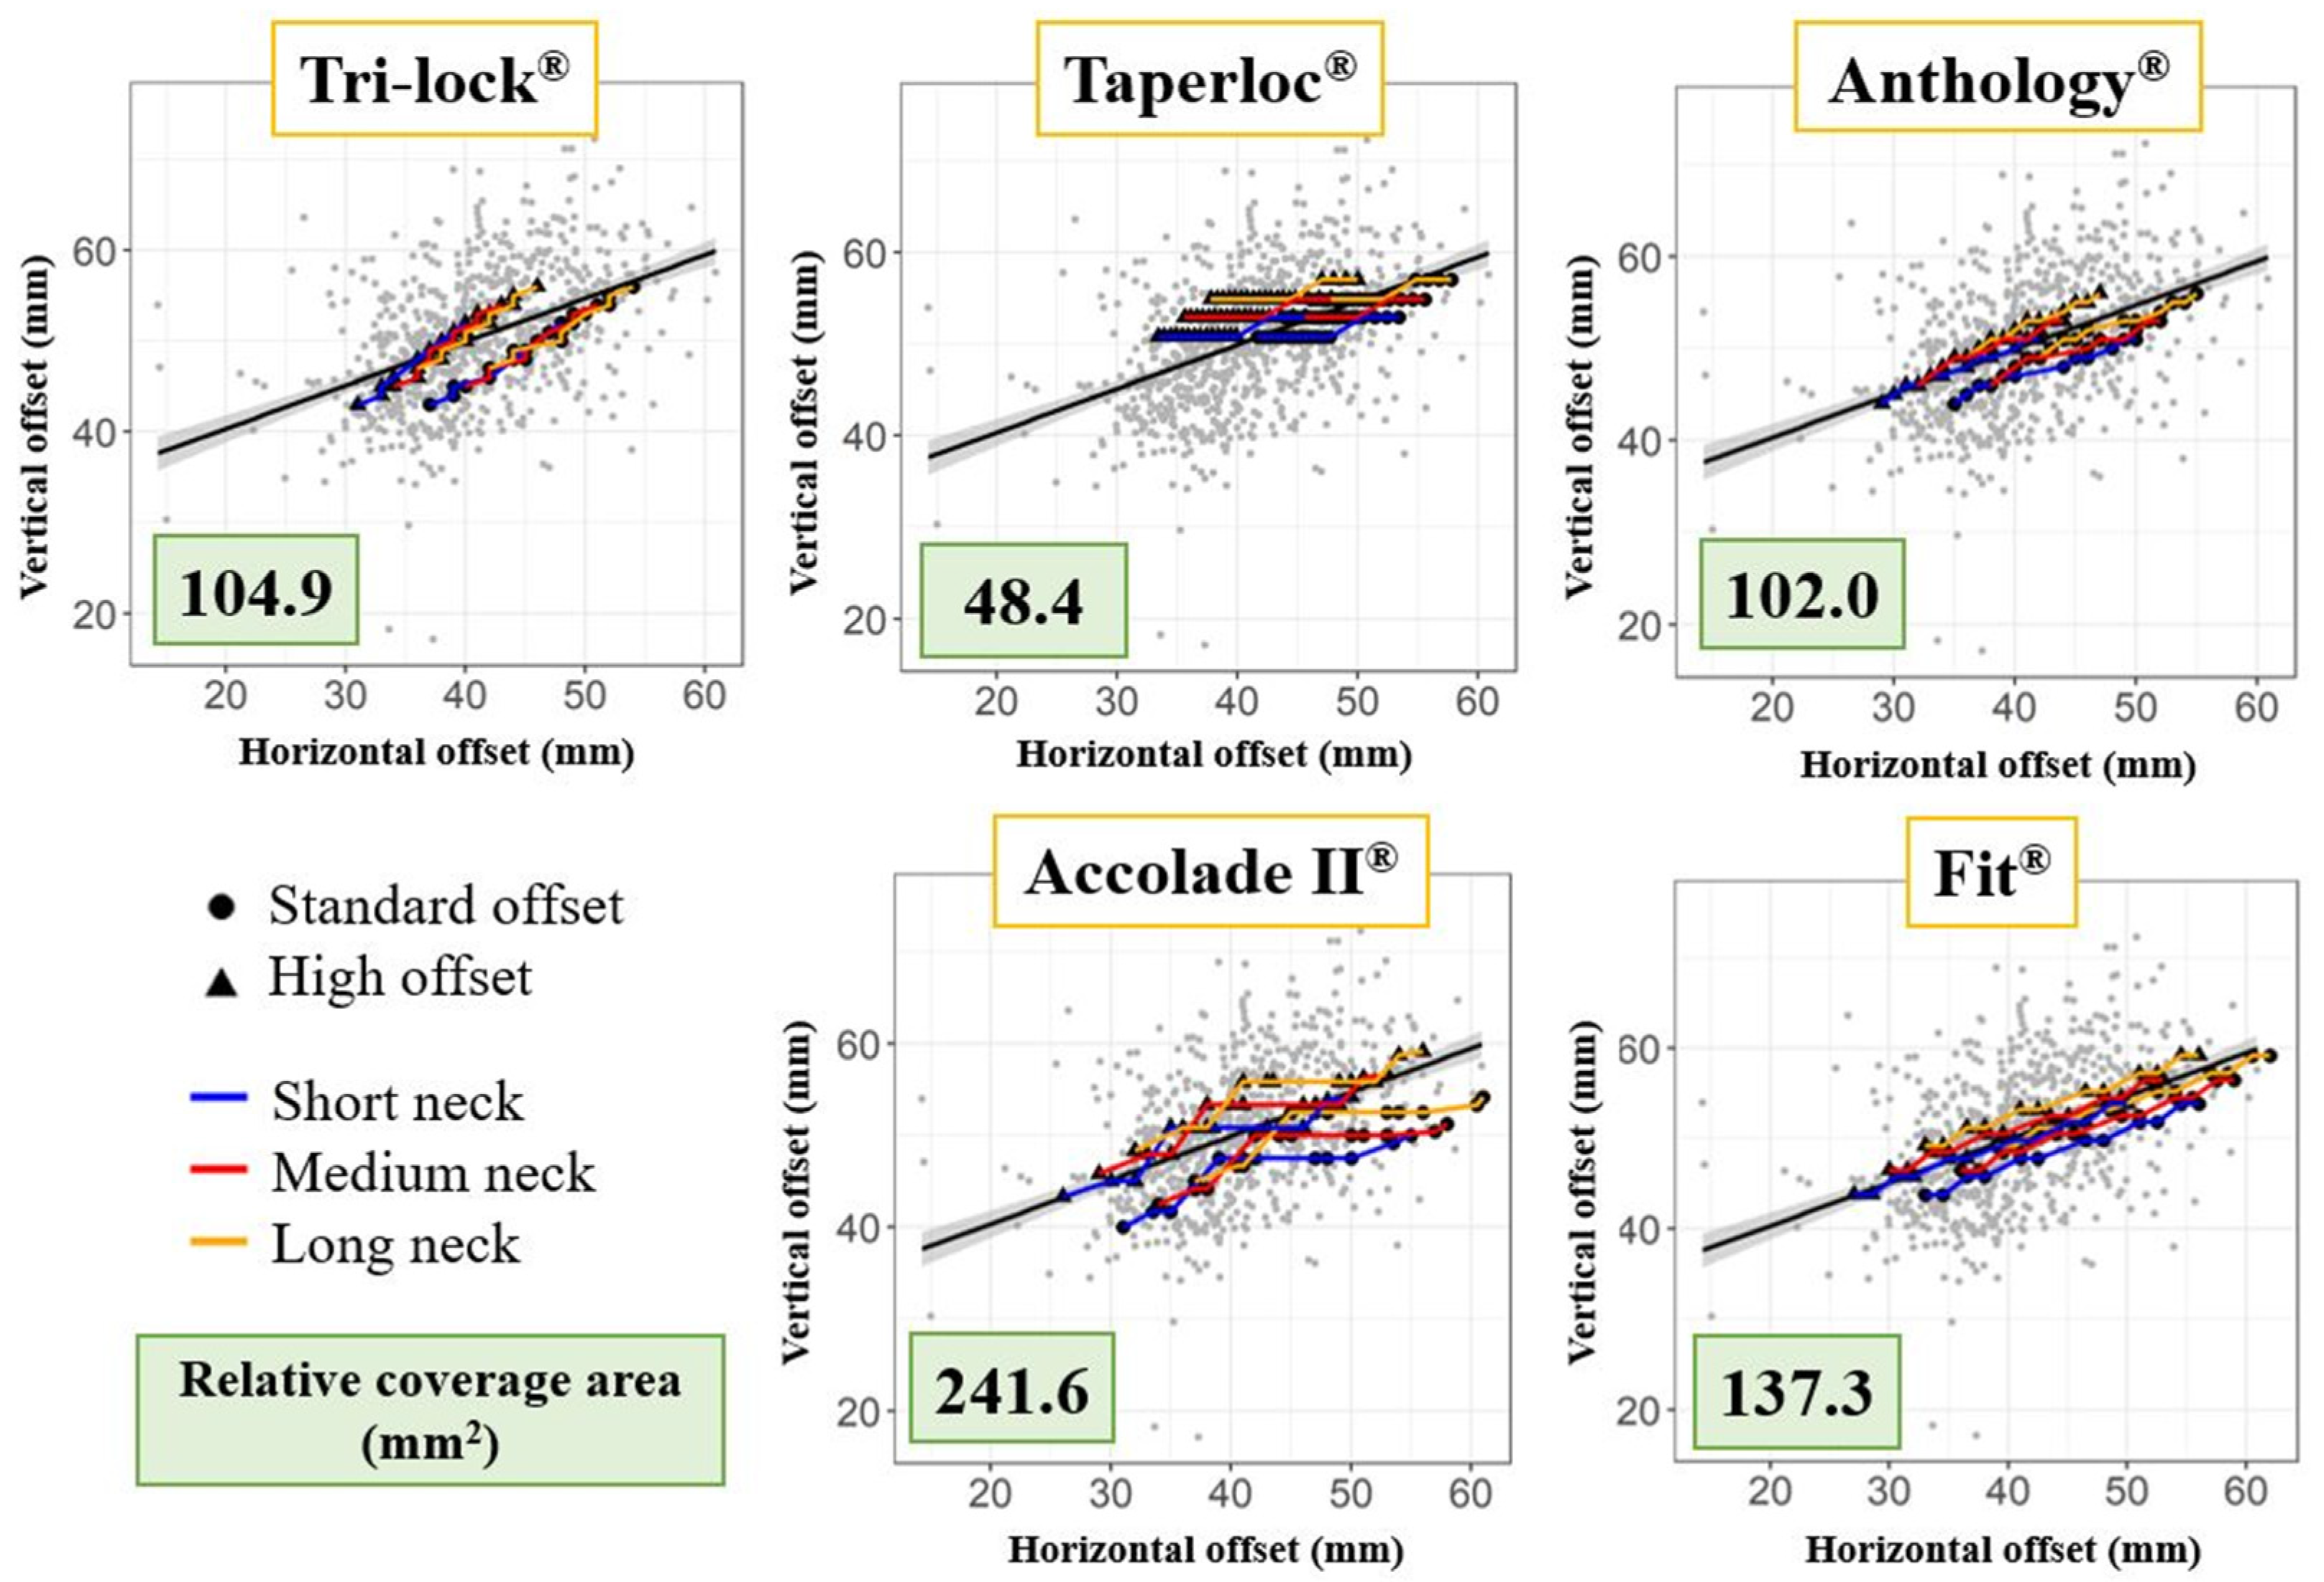

2.6. Offset Analysis

3.2. Offset Analysis

3.3. Fit Analysis